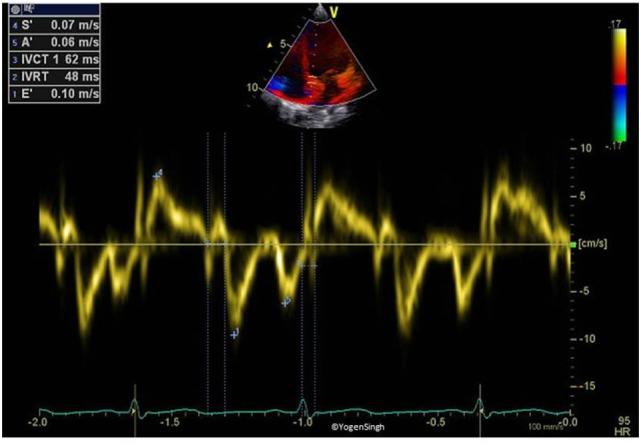

Hemodynamic instability and inadequate cardiac performance are common in critically ill children. The clinical assessment of hemodynamic status is reliant upon physical examination supported by the clinical signs such as heart rate, blood pressure, capillary refill time, and measurement of the urine output and serum lactate. Unfortunately, all of these parameters are surrogate markers of cardiovascular well-being and they provide limited direct information regarding the adequacy of blood flow and tissue perfusion. A bedside point-of-care echocardiography can provide real-time hemodynamic information by assessing cardiac function, loading conditions (preload and afterload) and cardiac output. The echocardiography has the ability to provide longitudinal functional assessment in real time, which makes it an ideal tool for monitoring hemodynamic assessment in neonates and children. It is indispensable in the management of patients with shock, pulmonary hypertension, and patent ductus arteriosus. The echocardiography is the gold standard diagnostic tool to assess hemodynamic stability in patients with pericardial effusion, cardiac tamponade, and cardiac abnormalities such as congenital heart defects or valvar disorders. The information from echocardiography can be used to provide targeted treatment in intensive care settings such as need of fluid resuscitation versus inotropic support, choosing appropriate inotrope or vasopressor, and in providing specific interventions such as selective pulmonary vasodilators in pulmonary hypertension. The physiological information gathered from echocardiography may help in making timely, accurate, and appropriate diagnosis and providing specific treatment in sick patients. There is no surprise that use of bedside point-of-care echocardiography is rapidly gaining interest among neonatologists and intensivists, and it is now being used in clinical decision making for patients with hemodynamic instability. Like any other investigation, it has certain limitations and the most important limitation is its intermittent nature. Sometimes acquiring high quality images for precise functional assessment in a ventilated child can be challenging. Therefore, it should be used in conjunction with the existing tools (physical examination and clinical parameters) for hemodynamic assessment while making clinical decisions.

血流动力学不稳定和心脏功能不全在危重症儿童中很常见。血流动力学状态的临床评估依赖于体格检查,并辅以心率、血压、毛细血管再充盈时间等临床体征,以及尿量和血清乳酸的测量。不幸的是,所有这些参数都是心血管健康的替代指标,它们提供的关于血流充足性和组织灌注的直接信息有限。床旁即时超声心动图可以通过评估心脏功能、负荷状态(前负荷和后负荷)和心输出量来提供实时血流动力学信息。超声心动图能够实时提供纵向功能评估,这使其成为监测新生儿和儿童血流动力学评估的理想工具。它在休克、肺动脉高压和动脉导管未闭患者的管理中不可或缺。超声心动图是评估心包积液、心脏压塞以及先天性心脏病或瓣膜疾病等心脏异常患者血流动力学稳定性的金标准诊断工具。超声心动图提供的信息可用于在重症监护环境中进行针对性治疗,如确定是否需要液体复苏还是使用血管活性药物支持、选择合适的血管活性药物或血管加压药,以及在肺动脉高压中提供特定干预措施,如选择性肺血管扩张剂。从超声心动图收集的生理信息可能有助于对患病患者做出及时、准确和适当的诊断并提供特定治疗。毫不奇怪,床旁即时超声心动图的使用在新生儿科医生和重症监护医生中迅速受到关注,现在它正被用于血流动力学不稳定患者的临床决策。与任何其他检查一样,它有一定的局限性,最重要的局限性是其间歇性。有时,在通气的儿童中获取高质量图像以进行精确的功能评估可能具有挑战性。因此,在做出临床决策时,应将其与现有的血流动力学评估工具(体格检查和临床参数)结合使用。